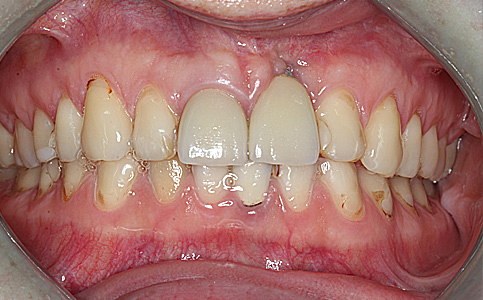

Przykład pełnej rehabilitacji protetycznej obejmujący leczenie biologiczne, uzupełnienie braków zębowych implantami oraz korony pełnoceramiczne w łuku górnym i dolnym. Spektakularna metamorfoza uśmiechu wykonana przez zespół Centrum Stomatologii i Ortodoncji FRESHmed odmieniła życie Pacjenta dodała pewności siebie i sprawiła, że z chęcią się uśmiecha.